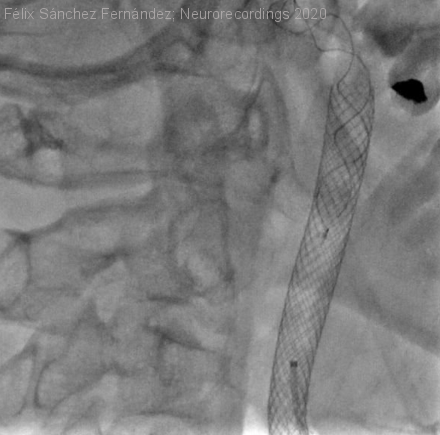

Disección carotídea asociada a distrofia muscular por alteración del colágeno VI

Hombre | 49 años

Diagnóstico final: Distrofia muscular por alteración del colágeno VI (LGMDD5)

Varón de 49 años en seguimiento por debilidad muscular lentamente progresiva, que precisa actualmente bastón. Varios miembros de su familia afectos con manifestaciones clínicas similares (madre, hermanos y primo por parte materna).